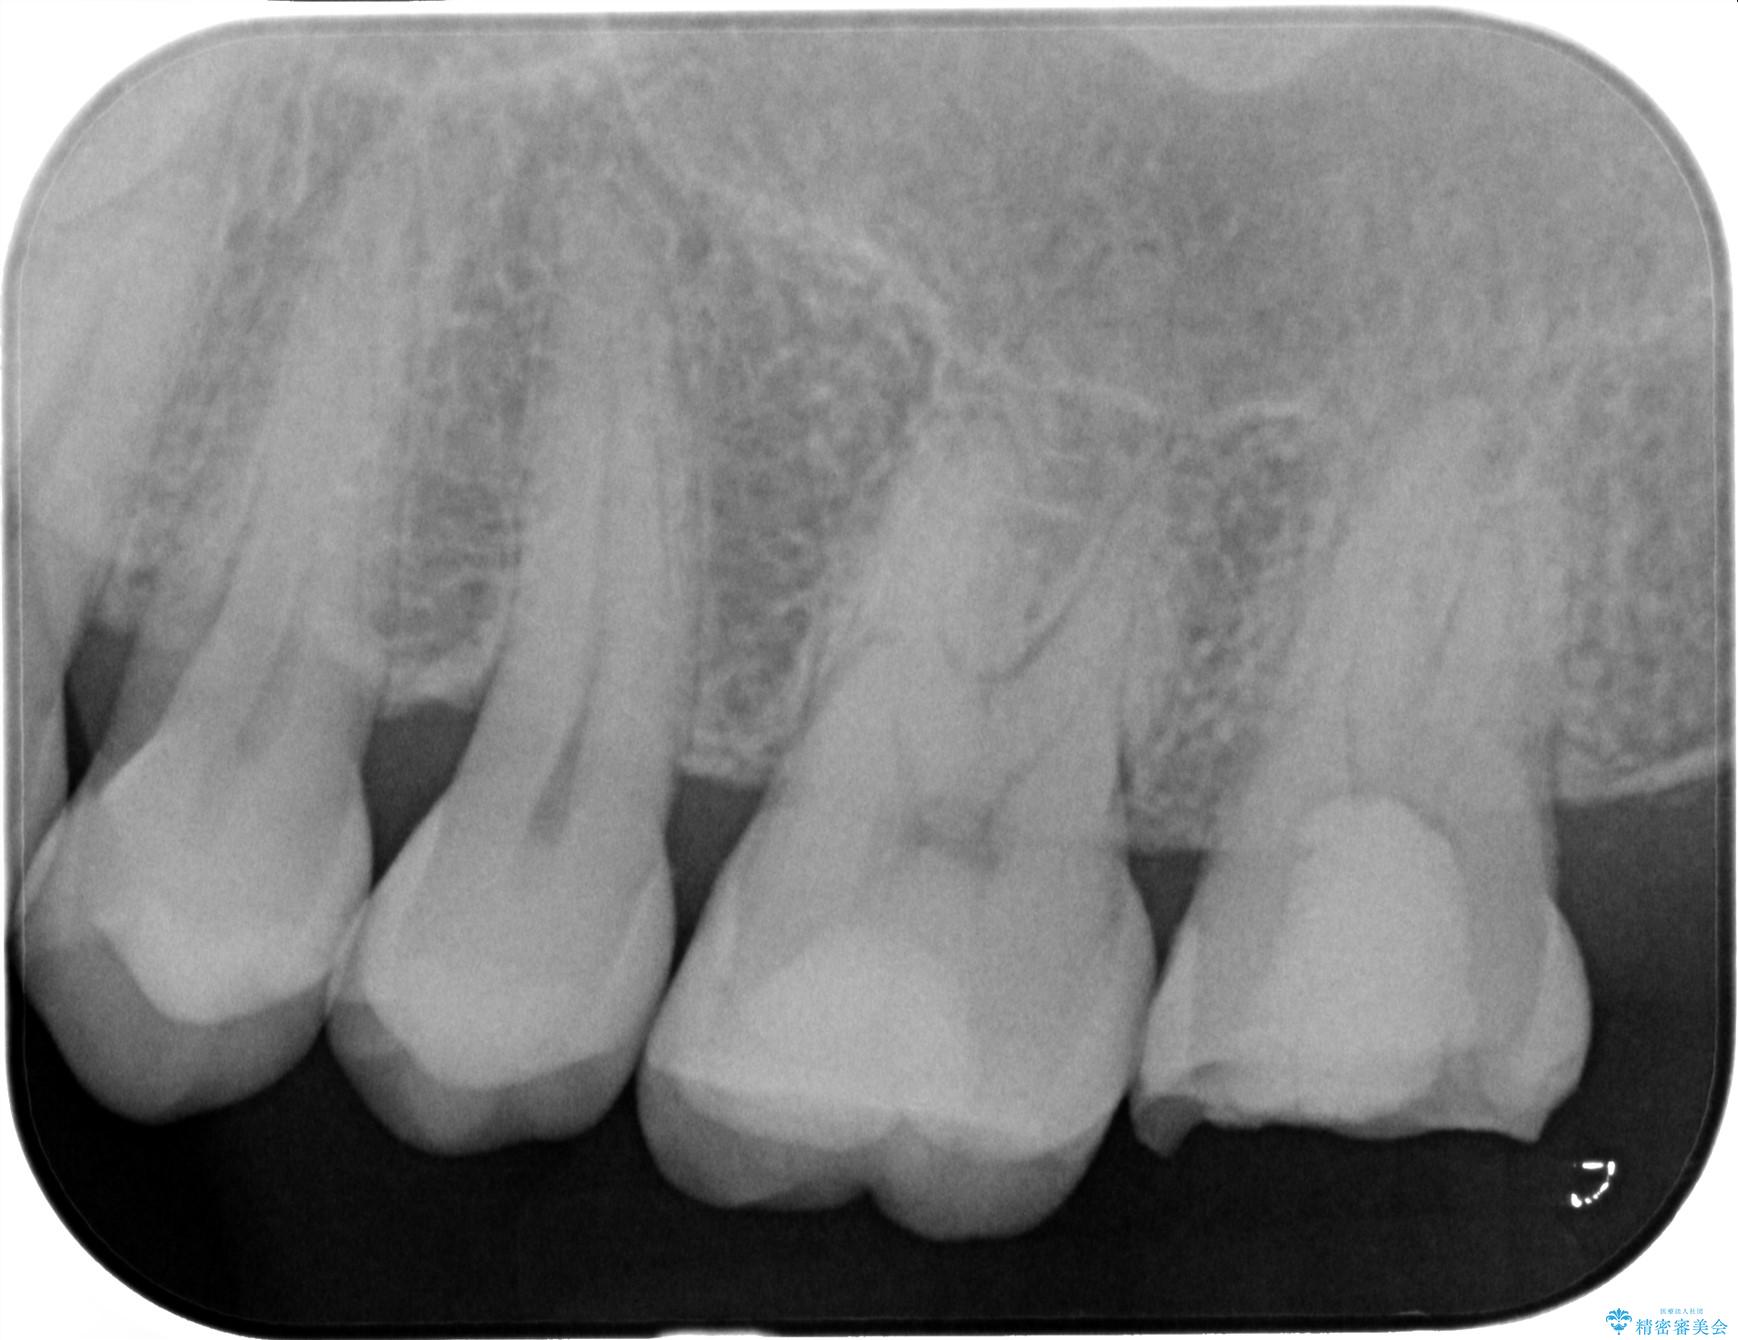

精査した結果、上顎奥歯は歯が割れてしまっており、根管治療ではなく抜歯の対象でした。

治療前

【噛むと歯が疼く】歯牙破折からのインプラント治療 治療前画像 【噛むと歯が疼く】歯牙破折からのインプラント治療 治療前画像 【噛むと歯が疼く】歯牙破折からのインプラント治療 治療前画像 【噛むと歯が疼く】歯牙破折からのインプラント治療 治療前画像 【噛むと歯が疼く】歯牙破折からのインプラント治療 治療前画像 【噛むと歯が疼く】歯牙破折からのインプラント治療 治療前画像 【噛むと歯が疼く】歯牙破折からのインプラント治療 治療前画像